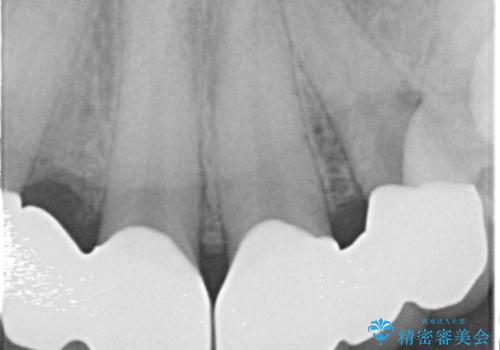

矯正以外の治療法で早く治したいとのご希望により、上顎両側犬歯を抜去しオールセラミックのブリッジによる補綴治療を行いました。

治療終了後、奥歯に残っていた矯正の接着剤を除去し、ホワイトニングも行いました。

クラウンの種類:オールセラミッククラウン スタンダード